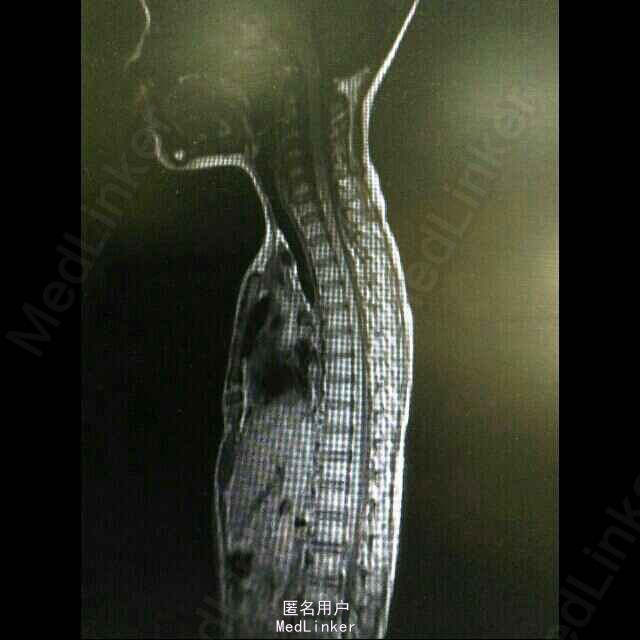

查体:T36.5℃,P105次/分,R26次/分。咽充血,双侧扁桃体II度肿大。 辅检:头颅MRI提示双侧额、顶叶、颢叶、枕叶多发异常信号灶,考虑感染性病变。血常规 : WBC 16. 13G/L, Hb114g/L, plt 417G/L ,N 72. 28 ,L18. 296, M 9. 016 。 病原体检测提示肺炎支原体感染,巨细胞病毒既往感染。CRP、PTC均提示细菌感染。免疫全套未见明显异常。视觉听觉诱发电位结果正常。 脑脊液WBC166,其他正常。颈胸段MRI未见异常。

诊断:炎症脱髓鞘性疾病:急性播散性脑脊髓炎ADEM。 处理:6-18入院后予以头孢他啶、更昔洛韦抗感染,营养脑细胞等对症处理。 6-21 开始激素冲击治疗,3天后逐步减量。 6-25 患儿激素治疗后仍有头晕,精神欠佳,查体双上肢肌力4级,双下肢肌力5级。予以丙球冲击治疗(1k/kg.d * 2天)

患者症状明显好转出院。 1、ADEM诊断根据感染或免疫接种后急性起病的脑实质弥漫性损害、脑膜受累和脊髓炎症状,因此,其临床症状和体征表现多样,有脊髓型,锥体外系型,小脑型等。 ADEM为单向病程,极少复发,预后好。 2、ADEM的MR特征:ADEM 主要累及脑和脊髓的白质,其MRI有一定特征,表 现为侧脑室周围及额颞顶枕白质内多发的斑点或斑片状病灶,部分可见“垂直脱鞘征”。病灶多不对称,长T1、长T2信号,边缘不锐利,直径多在1-2cm或略小。 3、ADEM临床表现与及MRI与首发的多发性硬化(MS)相似,需要鉴别诊断。MS多时相病程,反复发作,预后差,寡克隆区带出现率较高。MRI表现:MS 多仅累及脑室周围白质,极少累及丘脑。 脑灰质特别是丘脑是否受累可作为二 者的重要鉴别之一。常新旧病灶同时存在,新病灶强化而旧病灶不强化。